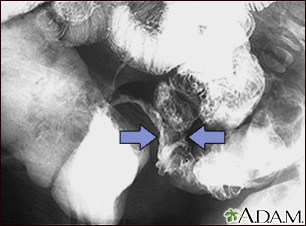

- Barium enema or upper GI (gastrointestinal) series